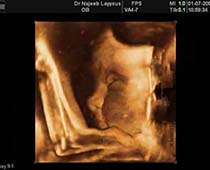

- Fetal Face Ultrasound Photos

- 3D Fetal Profile Ultrasound Scan Photos

- Fetal Parts Ultrasound Scan Photos

- 3D Fetal Limbs Ultrasound Scan Photos

- Fetal Behavior Ultrasound Photos

- The Clinical Advantages of 3D and 4D Ultrasound

- Definition and Features of Four Dimensional Ultrasound

- Uses of 4D Ultrasound scan

- The importance of 4D ultrasound imaging in pregnancy